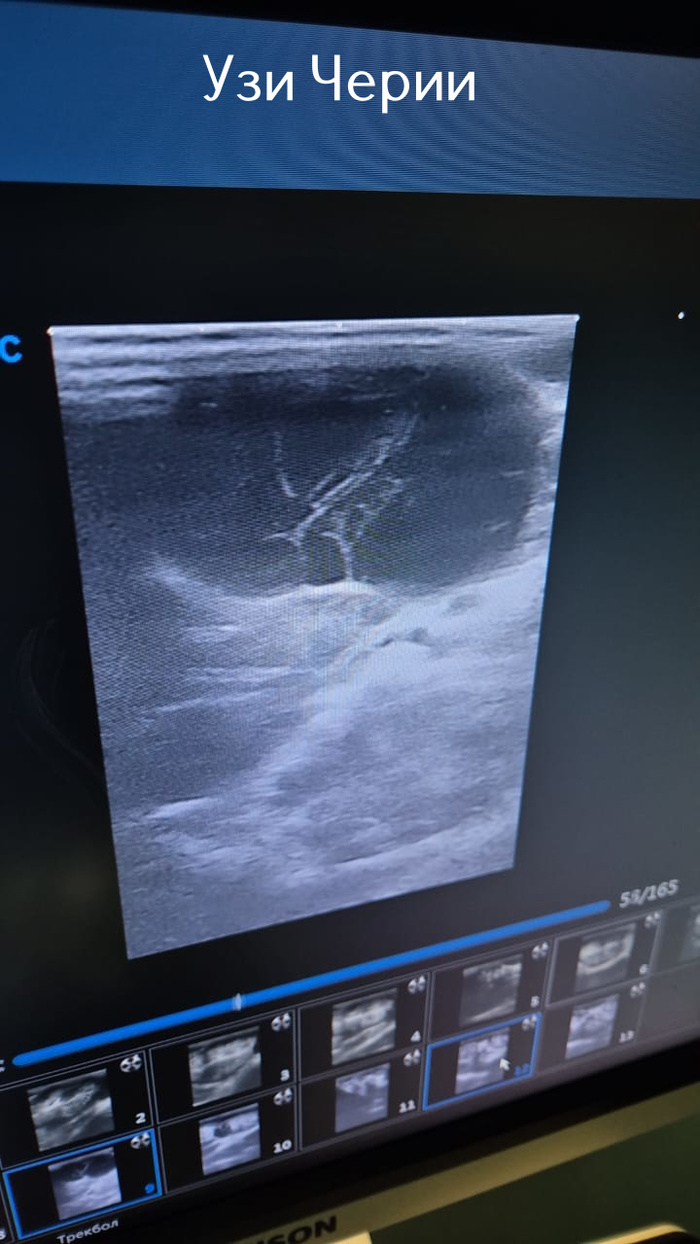

Вчера вечером отказалась от еды Черри. Сегодня утром ей стало хуже и уже в восемь утра её отправили в клинику. Там, в числе прочего, ей сделали УЗИ и выявили большое количество кист на почках. И какие-то спайки между почками. Решили сделать операцию и во время неё выяснилось что всё бесполезно и ей оставалось лишь несколько дней мучений... Черри теперь на радуге... Опять уже подзабытая боль в душе и в сердце навалилась. Если честно даже писать больше ничего не хочется сегодня. Этот текст уже час пытаюсь набрать...

Узи Черри